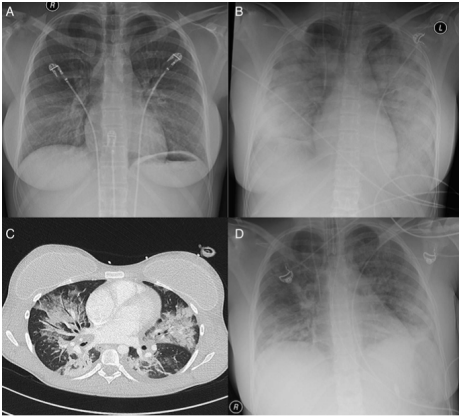

在一例55岁免疫功能正常女性患者中还可以看到两肺弥漫磨玻璃影和小叶中心结节,以小叶间隔增厚为主(图6)。并且该患者在5天内就得到了改善,没有其他病原体。另外一例22岁气急性胸痛5天患者的影像学也是双肺对称的磨玻璃影和实变(图7)

图片

图6  鼻病毒肺炎影像学表现(三)

图源:Tuberc Respir Dis, 2014, 77:132-135.